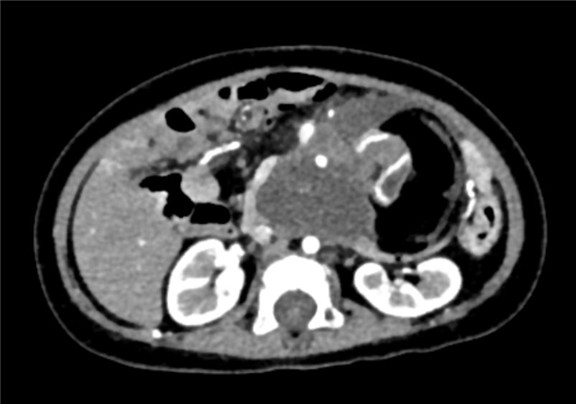

下腹部增强CT示:腹腔巨大占位,考虑畸胎瘤可能性大

术前CT检查:

静脉期